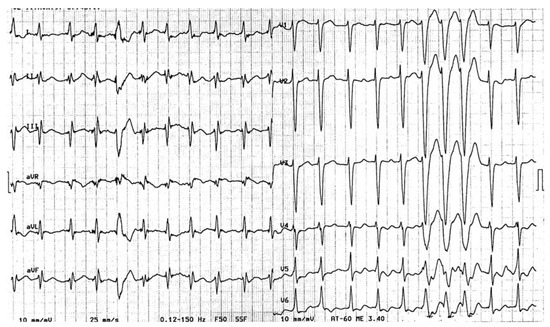

Tachycardie Ventriculaire?

by Jürg Schläpfer

Cardiovasc. Med. 2007, 10(4), 151; https://doi.org/10.4414/cvm.2007.01239 - 27 Apr 2007

Histoire clinique. Femme de 47 ans, connue pour des accès de fibrillation auriculaire (FA) paroxystique idiopathique traitée par flécaïnide 2 × 100 mg/j [...] Full article